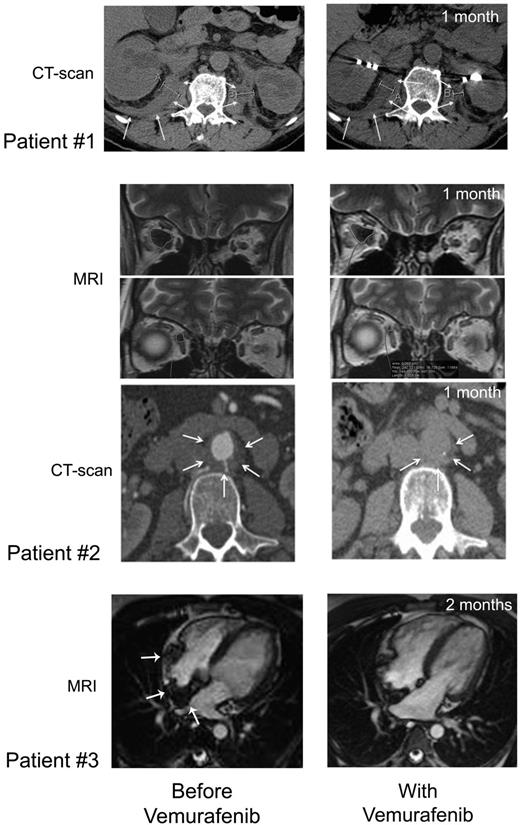

Figure 3

CT scan and MRI imaging assessment. Patient no. 1: Comparison of abdominal axial CT scans performed before (January 28, 2012; left) and on day 37 (May 23, 2012; right) of treatment showing regression of the infiltration around both kidneys (white arrows), evidenced by the decreased thickness (right kidney: 24.8 to 18.2 mm, left kidney 22 to 12.4 mm). Patient no. 2: Comparison of MRI performed before (left) and on day 36 (right) of vemurafenib treatment showing regression of ECD orbital infiltration. Comparison of abdominal axial CT scans performed before (March 29, 2012; left) and on day 39 (May 25, 2012; right) of vemurafenib treatment showing regression of the infiltration around abdominal aorta (white arrows): latero-aortic infiltration from 10.8 to 6.5 mm thick, and posterior infiltration from 6.5 to 4.6 mm thick. Patient no. 3: comparison of cardiac MRI, 4-chamber view: (A) February 21, 2012; see the infiltration of the atrial septum, the posterior wall and the free wall of the right atrium (white arrows); (B) July 19, 2012; note the regression of the infiltration.

Vemurafenib was started at 1920 mg/d (b.i.d.) on April 19, 2012 and was tapered to 960 mg/d from day 30 due to erythema, and was thereafter maintained at this dose. Within a few days of the initiation of treatment, itching disappeared. Evaluation on day 30 showed an improvement of creatinine (190 to 161μM), GGT (936 to 300 U/l) and alkaline phosphatase (644 to 177 U/l) values. On day 62, GGT was 183 U/l, PAL 146 U/l, and creatinine 170μM. CRP was normalized by day 30 (Figure 4), and remained under 5 mg/L on day 62. PET was performed after 30 days of vemurafenib treatment and the findings compared with those obtained 4 months earlier: there was a substantial improvement of all lesions (Figure 1), with a mean Standardized Uptake Value (SUV) change of −70% (range, −66% to −80%); the change within soft tissue and bone was similarly −70% (range, −51% to −78%; supplemental data, available on the Blood Web site; see the Supplemental Materials link at the top of the online article). Thoraco-abdominal CT after 37 days of treatment showed a significant reduction of periaortic infiltration (Figure 3). This cannot be attributed to PEG-IFN treatment, withdrawn on March 31, 2012, because several other markers clearly indicated that the patient was a nonresponder (high CRP values, hydronephrosis and pyelocalicial dilation, worsening of PET findings). Hydronephrosis and pyelocaliceal dilation resolved completely. Note that the PET assessment at 4 months showed that the decrease of FDG uptake had been sustained: uptake was lower than that observed after the first month (Figure 1). Aortic MRI after 4 months disclosed a marked regression of peri-aortic sheathing relative to that observed by CT-scan in May 2012. The CRP value remained low on day 123 of treatment (Figure 4).

After a few days, histiocytic skin lesions resolved (Figure 2), and the pain in the right eye disappeared such that morphine could be stopped. A new skin biopsy confirmed the absence of histiocytic infiltration of the epidermis and hypodermis. CRP was normalized by day 30 (Figure 4), and was 5.2 mg/L (N < 5) on day 48. PET 31 days after initiation of vemurafenib was compared with that performed 2 months earlier: the change in the mean SUV was −57% (range, −51% to −67%) and that in soft tissue and bone was −70% (range, −56% to −78%; Figure 1 and supplemental data). Orbit MRI on day 36 showed a 26% to 66% decrease of the retro-orbital infiltration (Figure 3 and supplemental data). Thoraco-abdominal CT on day 39 demonstrated a 30% to 40% decrease of the posterior and lateral peri-aortic infiltration (Figure 3), and the absence of the previously observed interlobular septa thickening, characteristic of pulmonary involvement of ECD. The CRP value remained below 5 mg/L on day 141 of treatment (Figure 4), and the patient was asymptomatic, with the absence of orbital pain.

Vemurafenib was administered at 1920 mg/d (b.i.d) from May 9 to May 29: the dose was tapered to 960 mg/d (b.i.d) due to pilar keratosis and erythema. One month later, the CRP level was 10 mg/L, the thickeness of xanthelasmas had diminished, and PET displayed significantly decreased uptake in the basilar region and by the long bones. In July 2012, the CRP value was normal. The most striking feature was the significant improvement of the cardiac MRI on July 19: right atrial wall infiltration had regressed substantially (Figure 3). On day 119 of treatment, the CRP value was still low, at 8 mg/L (Figure 4).